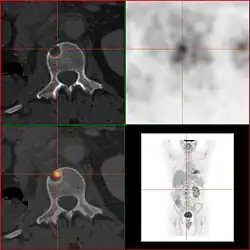

2-FDG wird in der PET für die Diagnose,[24] Staging (Stadienbestimmung), Therapieeinstellung und Therapiekontrolle verwendet. Man spricht in diesem Zusammenhang auch oft von der „FDG-PET“. 2-FDG ist als Diagnostikum eine außerordentlich nützliche und vielfach bewährte Verbindung. Die Anwendung hat einen rein diagnostischen Hintergrund. Genutzt wird dabei die bei der Paarvernichtung (Annihilation) von Positron und Elektron entstehende Vernichtungsstrahlung. Bei der Annihilation entstehen zwei hochenergetische Photonen, die eine Energie von 511 keV haben und in einem Winkel von 180 Grad zueinander, ausgesandt werden. Für die Therapie (Strahlentherapie, in diesem besonderen Fall würde man von einer Endoradiotherapie sprechen) sind die für die Diagnostik genutzten Gammaquanten nicht geeignet.

Für die FDG-PET gibt es drei Hauptindikationen für die Untersuchung von Patienten mit onkologischen Erkrankungen:[19] die Differenzierung zwischen benignen oder malignen (gutartig oder bösartig) Tumoren, das Tumorstaging bezüglich der Lymphknoten und Fernmetastasen sowie die Differenzierung Narbengewebe/vitales Tumorgewebe (Rezidiv, residueller Tumor). Die FDG-PET wird in der Onkologie zur Untersuchung von Lungenkrebs, dem kolorektalem Karzinom, Speiseröhrenkrebs, Magenkrebs, Kopf-Hals-Karzinom, Gebärmutterhalskrebs, Eierstockkrebs, Brustkrebs, dem malignen Melanom und den meisten Arten von Lymphomen eingesetzt.[31] Insbesondere sehr langsam wachsende Tumoren weisen in der Regel keine wesentlich erhöhte FDG-Aufnahme aus. Eine FDG-PET-Untersuchung ist dann meist nur in Ausnahmefällen sinnvoll.[19] Dazu gehören Prostatakarzinome, differenzierte neuroendokrine Tumoren (z. B. Karzinoid), bronchoalveoläre Karzinome, niedrig maligne Non-Hodgkin-Lymphome, niedrig maligne Hirntumore (Astrozytom II, Oligodendrogliom II) und das Leberzellkarzinom (vor allem höher differenzierte Formen). Entzündungen bzw. Heilungen zeigen neben dem Tumorgewebe ebenfalls eine erhöhte Stoffwechselaktivität und somit eine erhöhte FDG-Aufnahme. Eine Untersuchung zur Differenzierung beispielsweise von Abszessen und Tumorgewebe, Sarkoidose, Bronchialkarzinomen usw., kann deshalb mit 2-FDG kaum sinnvoll durchgeführt werden.[19]